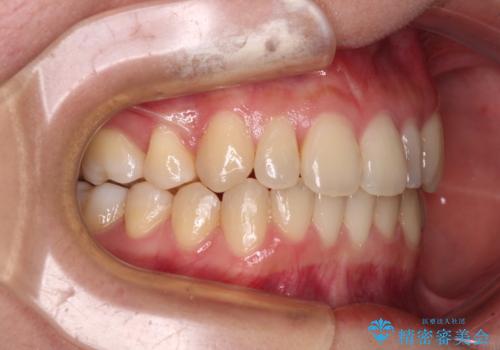

八重歯の抜歯矯正 補助装置を用いたインビザライン矯正

- 上顎の重なっている前歯を気にして来院された患者様です。

重なっている部分は抜歯が必要で、歯の移動量が多く、更には右側にずれている正中を改善する必要がありました。

インビザライン単体での治療は困難と判断し、補助装置により八重歯移動後にインビザラインを用いることとしました。

非常にしっかりとマウスピースを装着してくださいましたが、前歯の排列がなかなか仕上がらずに期間がかかってしまいました。